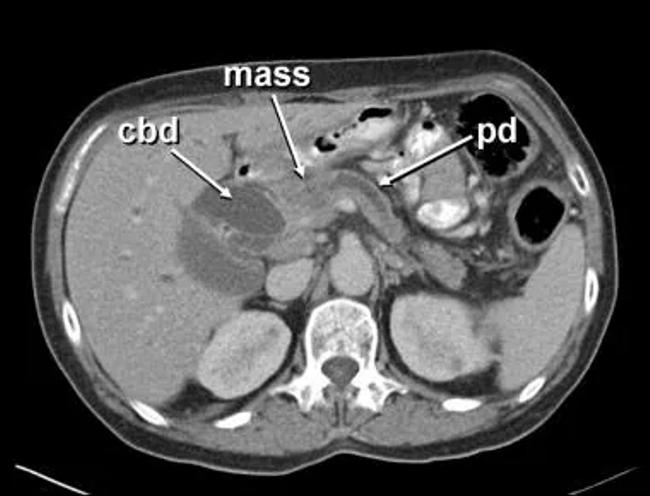

52yo male with abdominal and back pain.

Obstructive Jaundice

• secondary to pancreatic carcinoma

• underwent Whipple's procedure

• note the rise in GGT with obstruction.